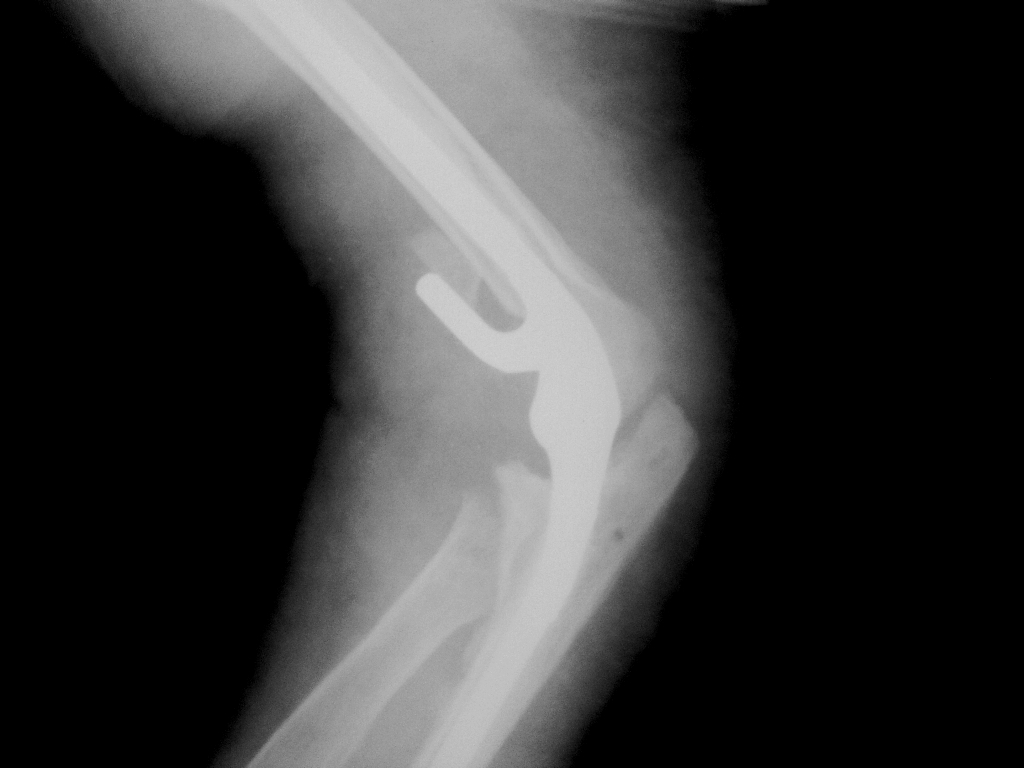

Круто. Локоть я ни разу не видел.

Я тоже))) Почин удался.

Было ограничение разгибания (по прямому снимку видно, что не полное), сейчас в полном объеме, разработка на 2-й день началась. Боли в 1-й день после операции купировались анальгетиками, сейчас в/м отменены.

А как вы описываете подобные снимки? Что важно отразить в протоколе?

"Состояние после эндопротезирования ... сустава - удовлетворительное." Честно говоря, я считаю, что дело рентгенолога зафиксировать протезирование, определиться с нормальностью оси конечности, наличием экструзии цемента, если таковой применялся. Грубых ляпов, ошибок мне посчастливилось не видеть.

Если видится что-то не так, иду к травматологам и выясняю, что мне пригрезилось)). Про локтевой эндопротез данные скудные, ново. Но я думаю, что также, как и с другими суставами - ось, соотношение в суставе.